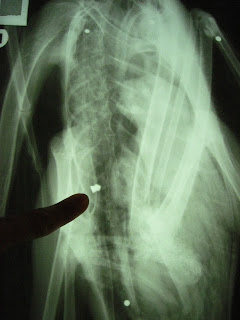

The bird came to us emaciated and weak, but with no apparent injuries. We suspected lead poisoning might be the problem and upon x-ray, the VINS Wildlife Services department found the bird to be riddled with bird shot (see photo; x-ray courtesy of Kedron Valley Veterinary Clinic in Woodstock, VT), including a pellet from a pellet gun we believe contained lead. Luckily, the lead pellet was not in the bird’s gizzard, which would have caused severe lead poisoning. We did treat the bird for lead, and also with several medications to treat his heavy parasite load (most wild birds carry parasites).